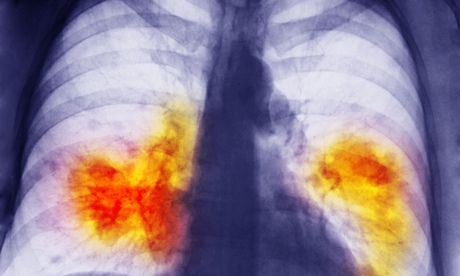

An x-ray showing lung cancer.

An x-ray showing lung cancer. UK lung cancer survival rates are just under 10% by the end of five years – but most other countries do not exceed 20%. Photograph: Smc Images/Getty Images

Lung cancer survival rates are worse in every part of the UK than in most of Europe and other wealthy countries, while breast cancer survival is now up with the best, according to a study comparing outcomes around the world.

The Concord-2 study studied data from 67 countries relating to 25.7 million adults and 75,000 children with cancer. It found substantial differences in five-year survival rates, not only between the developing and developed world, but also within the more affluent regions of Europe and North America. Survival rates in the UK for lung cancer are under 10% by the end of five years.